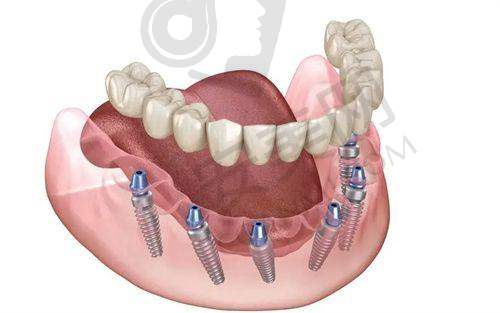

韩国登腾种植牙是国内外有名的种植牙品牌。它采用了精良的表面处理技术,能够促进种植体与牙槽骨的快速结合,大大缩短了种植体的愈合时间。登腾种植牙的稳定性非常好,能够承受较大的咀嚼压力,确保患者在日常生活中正常使用。而且,它的生物相容性高,能够减少人体对种植体的排异反应,降低感染等并发症的发生几率。此外,登腾种植牙的外观与天然牙齿非常相似,能够达到自然美观的成效,让患者在拥有健康牙齿的同时,也能拥有自信的笑容。

首先,患者需要到乌鲁木齐美奥口腔进行全方面的口腔检查,包括口腔CT扫描等,以确定患者的口腔状况和种植方案。然后,王旭医生会与患者进行详细的沟通,解释种植方案的具体内容和注意事项,患者可以根据自己的情况进行选择和调整。接下来就是种植手术阶段,在局部麻醉下,王旭医生会将韩国登腾种植体植入患者的牙槽骨内。手术后,患者需要按照医生的嘱咐进行休息和护理,等待种植体与牙槽骨愈合。一般需要几个月的时间,待种植体稳定后,再安装全瓷冠。末尾,医生会对患者进行复查,确保种植成效达到预期。